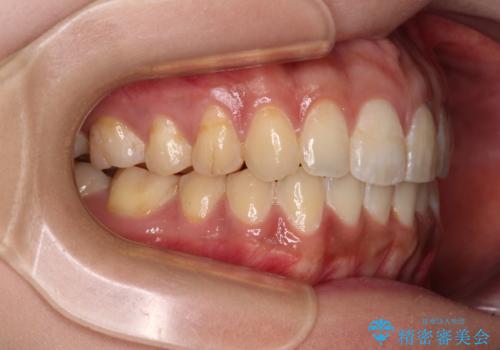

- 前歯のデコボコと上下前歯の隙間を気にして来院された患者様です。

下顎前歯はデコボコのため、歯肉が腫れやすくなっていました。

また、舌突出癖のため、上下前歯の間に隙間ができてしまい、上顎前歯が前方に傾斜している状態でした。

舌のトレーニングをしっかりと行っていただき、上下前歯をしっかりと接触させることができました。